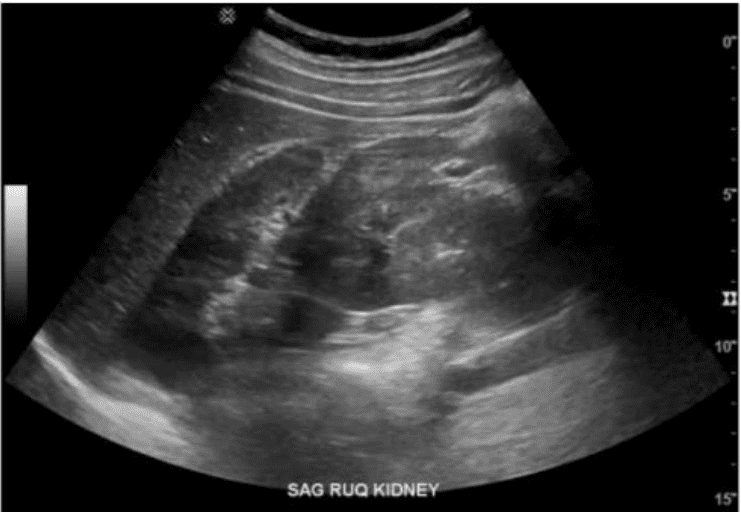

Which renal anomaly is demonstrated on this image?